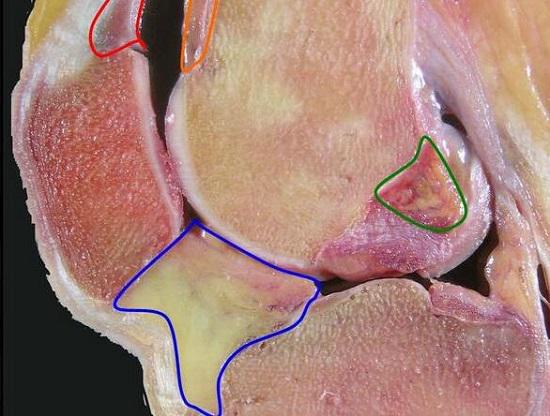

针对I型膝关节纤维化而言,切除操作多集中在关节前方的前交叉韧带附近,进行切除后,使髁间窝能够彼此卯合即可达到治疗目的。II型膝关节纤维化通常会有更多的瘢痕和纤维化组织,这些组织可能位于胫骨近端前方滑囊处及前交叉韧带附近,切除后要确认膝关节是否可以伸直,是否存在上下髁撞击,并根据情况决定是否采取其他外科手段。III型膝关节纤维化通常伴有髌骨活动度的下降,这不仅与瘢痕和增生有关,还可能存在髌骨与软组织粘连的问题。III型与II型在胫骨上端前方的情况相近,但III型可能同时存在脂肪垫的纤维化,可能需要将髌腱及髌骨与其下方的瘢痕组织分离,瘢痕切除的范围可能需要扩大到半月板前角,乃至股内侧肌和外侧肌的纤维囊,以获得髌骨和髌腱的全面松解。IV和III型的情况相近,但IV型的髌骨粘连范围可能会更加靠上。III型和IV膝关节纤维化的手术治疗后,应根据情况对髌骨及髌腱实施推拿、牵拉等物理疗法,以帮助髌骨和髌腱获得合理的运动力学特性。